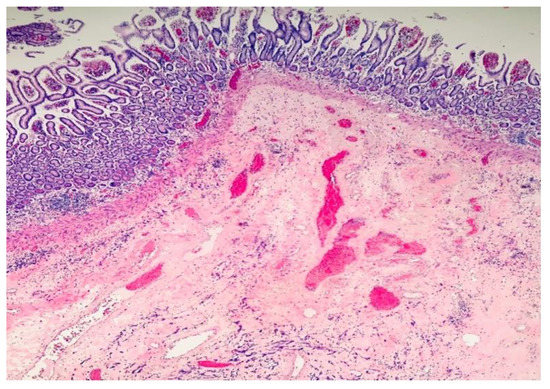

2. Case Report and Evolution